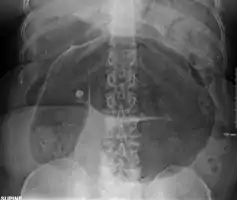

After taking a thorough history, the diagnosis of colonic volvulus is usually easily included in the differential diagnosis. Abdominal plain x-rays are commonly confirmatory for a volvulus, especially if a "bent inner tube" sign or a "coffee bean" sign are seen. These refer to the shape of the air filled closed loop of colon which forms the volvulus. Should the diagnosis be in doubt, a barium enema may be used to demonstrate a "bird's beak" at the point where the segment of proximal bowel and distal bowel rotate to form the volvulus.

This area shows an acute and sharp tapering and looks like a bird's beak. If a perforation is suspected, barium should not be used due to its potentially lethal effects when distributed throughout the free infraperitoneal cavity. Gastrografin, which is safer, can be substituted for barium.